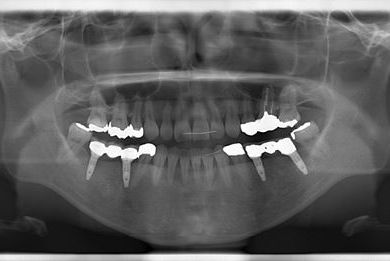

インプラントの症例写真 IMPLANT

抜歯即日スピードインプラント治療

| 性別/年齢 | 女性 / 37歳 | ||||||||||||||||||||||||||||||||

| 主訴 | ブリッジの支えとなっている歯が虫歯になり、ブリッジが難しくなったため、インプラントか義歯かの相談で来院。 | ||||||||||||||||||||||||||||||||

| 治療方針 | 抜歯と同時にインプラント治療を行い、治療期間を短縮する。 | ||||||||||||||||||||||||||||||||

| 治療内容 | インプラント4本(抜歯即日スピードインプラント治療)、ハイブリッドセラミッククラウン6本 | ||||||||||||||||||||||||||||||||

| 総治療費 | 1,236,165円 | ||||||||||||||||||||||||||||||||

| 治療期間 | 1年5ヶ月 |